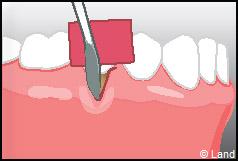

LES TECHNIQUES AVEC APPORT DE GENCIVE OU « GREFFE DE GENCIVE » :

Elles font appel à un prélèvement sur le patient à un endroit où elle est en excès, qui est ensuite posé sur la récession.

Il y a 2 types de « greffes » de gencives :

Les greffes épithélio-conjonctives :

Elles sont pratiquées pour des zones non esthétiques de la cavité buccale, à cause de l’aspect « rustine» que la cicatrisation leur confère.